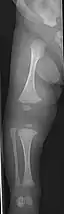

Left forearm

Right forearm

Right femur

Four X-rays of a 24-year-old American man, who had had more than one hundred bone fractures in his lifetime, and received a childhood clinical diagnosis of type IV–B OI. Genetic diagnosis in 2018 identified a previously uncatalogued pathogenic variant in the gene which encodes proα2(I) chains of type I procollagen, COL1A2, at exon 19, substitution c.974G>A. Due to childhood neglect and poverty, subject never received surgery to implant intramedullary rods. Malunions are evident as the humerus and femur were broken in adolescence but orthopedic care did not follow. Severe scoliosis, as well as kyphosis, are also evident. The unavoidably low contrast in the film is due to a combination of subject's obesity and low bone mineral density (BMD). Subject's BMD Z-score was -4.1 according to results of a dual-energy X-ray absorptiometry (DXA) scan also done in 2018.